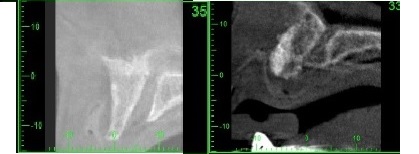

17/21 - CT scan 6 months post-op: Stable bone with Ø 8mm width

Reconstruction of maxillary ridge with maxgraft® block - Amit Patel